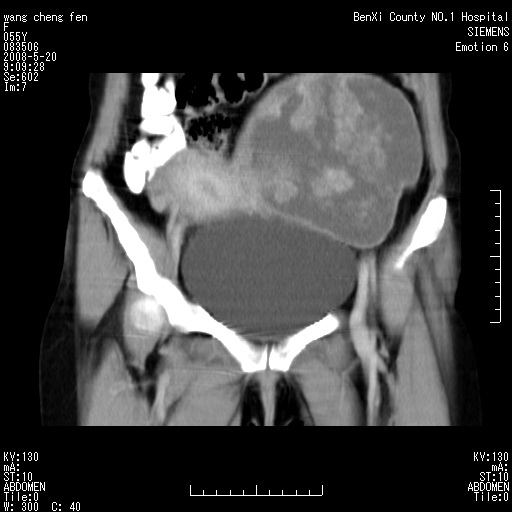

标题: CT3539:盆腔巨大肿瘤增强 [打印本页]

标题: CT3539:盆腔巨大肿瘤增强

女、绝经后阴道流血3个月

左侧附件区巨大囊实性病灶,边缘光整,病灶囊壁较厚,增强示囊壁及实性部分明显强化,强化呈度与宫体实质大致相同,宫腔积液征像,未见盆腔积液等其他异常,考虑左侧卵巢囊腺癌,不除外囊腺瘤及浆膜下肌瘤坏死

左侧附件区巨大囊实性病灶,边缘光整,病灶囊壁较厚,增强示囊壁及实性部分明显强化,强化呈度与宫体实质大致相同,宫腔积液征像,未见盆腔积液等其他异常。绝经后阴道流血3个月,结合病史左侧卵巢囊腺癌首先考虑,宫腔扩大不除外累及。期待结果。

支持浆膜下子宫肌瘤.之前由于网络原因未看全图片,现在重看,宫颈见一类圆形低密度影,增强轻度强化,低于肌层强化,宫腔扩大,考虑宫颈癌伴宫腔积液可能性大.

1,宫颈部占位,宫颈癌?2,左侧附件区囊实性占位,界较清,实质部分强化明显。考虑浆膜下或阔韧带肌瘤囊变可能大。囊腺类肿瘤不除外。